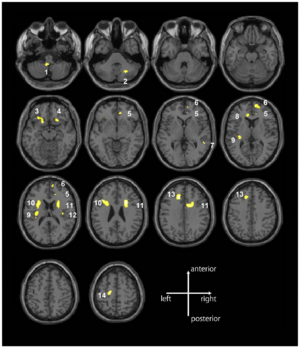

Inhibited adults have larger amygdalae. (A) Average manually traced amygdala displayed in 3D. (B) Overall amygdala volume was greater in the inhibited compared with the uninhibited group in the right amygdala (inhibited: 2277 ± 62 mm3; uninhibited: 2101 ± 59 mm3; P = 0.045). (C) In the inhibited group, shape analysis reveals areas of greater convexity in the left and right amygdala. The peak areas of convexity are shown in red. Group differences in surface amygdala shape are displayed on an average amygdala surface. (D) Inhibited adults had regions of significantly larger gray matter volume in both the left and right amygdalae (P < 0.05 FWE corrected at the cluster level). For the left amygdala, the significant cluster was 442 voxels (35% of 1252 voxels; peak voxel: x = −21, y = −4, z = −16). For the right amygdala, the significant cluster was 402 voxels (33% of 1217 voxels; peak voxel: x = 18, y = −3, z = −22). Areas of significant between-group differences are illustrated on multiple coronal slices of an average brain. Amygdala volume was estimated for each of the subjects in 3D Slicer, Version 3.4. |